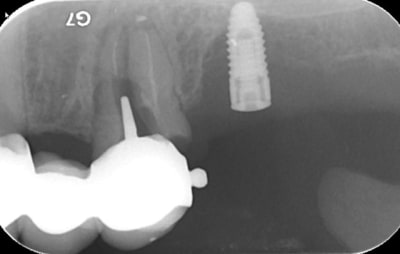

bon, c'est le cas clinique d'un pote (sera peut être plus ensuite, qui sais...) qui c'est décidé de venir me voir suite à un problème sensé être réglé par son praticien habituel au niveau de sa 12 (et 11)

j'attends les images scan pour voir l'ampleur de problème, mais c'est pas jojo...

c'est fistualisé donc c'est plus douloureux...n'empêche qu'il va y avoir du sport amha...

je pense que dans un premier temps, il va falloir aller nettoyer tout çà (et virer le cône de gutta qui dépasse) donc voie chir, obturation à rétro des 2 dents dans la séance

le passé est "lourd" sur ces dents, traitement endo, retraitements (plusieurs au moins 2 ou 3 pour chacune)

chir apicale aussi

bref, çà traine depuis un long long moment...

donc: intervention de la "dernière chance" si les images 3D sont pas trop cata...

au minimum: aller cureter tout çà + chir à rétro avec pourquoi pas comblement/membrane

le but: ne plus perdre d'os...parce qu'amha çà va se finir avec du titane....

je viens d'avoir les images...

autant sur la 11 çà paraît jouable...autant sur la 12 je pense que c'est mort!!!

faux canal, il ne reste quasi plus rien de la partie vestibulaire de la dent...

point positif: il semblerait que j'ai encore de quoi ancrer une vis sous les fosses nasales en apical de cette 12...

donc amha çà sent l'EII avec mise en vitrine immédiate...et si c'est le cas, je ne ferai pas de quartier à la 11...elle passera elle aussi à la trappe vu le risque de récidive et/ou de contamination du biomat qu'il me faudra mettre pour éviter que tout ne s'effondre...